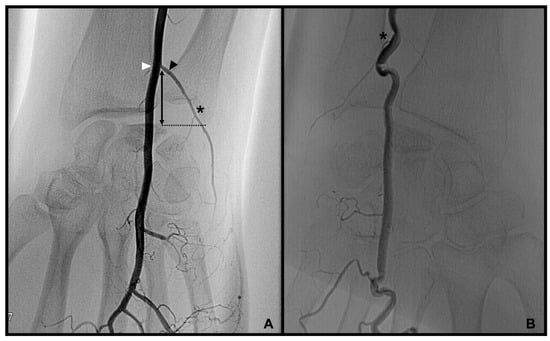

3.1. Palmar Radiocarpal Artery and Palmar Radiocarpal Arch (PRCA)

distance from the DCBUA to the styloid process of the ulnar (DCBUA = dorsal carpal branch of the ulnar artery).